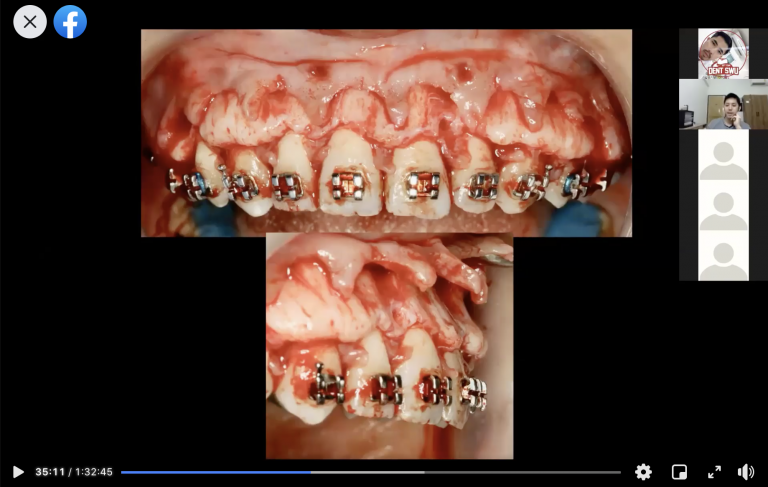

ตัวอย่างผู้ป่วยรายที่1

ตัวอย่างผู้ป่วยรายที่2

ตัวอย่างผู้ป่วยรายที่3

1.Full thickness flap reflection

2.Decortication

3.Bone grafting (autogeneous and/or allograft and/or xenograft and/or alloplast ขึ้นอยู่ทำความpreferของoperator) stepนี้จะใช้membraneด้วยหรือไม่ก็ได้

4.Flap closure